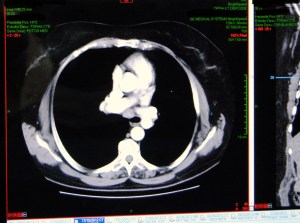

Over the continuing course of his treatment, a large opening on the anterior chest was created surgically.  Due to the extent of necrotic tissue, this required the removal of anterior sections of ribs #2, 3, 4 and 5, leaving the patient with a very large open cavity, as seen in CT slices (pulmonary and tissue windows).

BPF CT1

packing material can be seen in the right chest cavity.

tissue window showing extent of wound

This large cavity was left open for a period of around two years, while infected material was debrided and evacuated, and aggressive wound management was continued.  At the time of his presentation to the operating room, the wound bed is dry and pink with a small amount of slough.  An opening to the bronchus is visible (with bubbling on respiration at the site of the wound). The wound measures approximately  6 cm X 4 cm.  As seen from the CT images above, the wound was also several centimeters in depth.